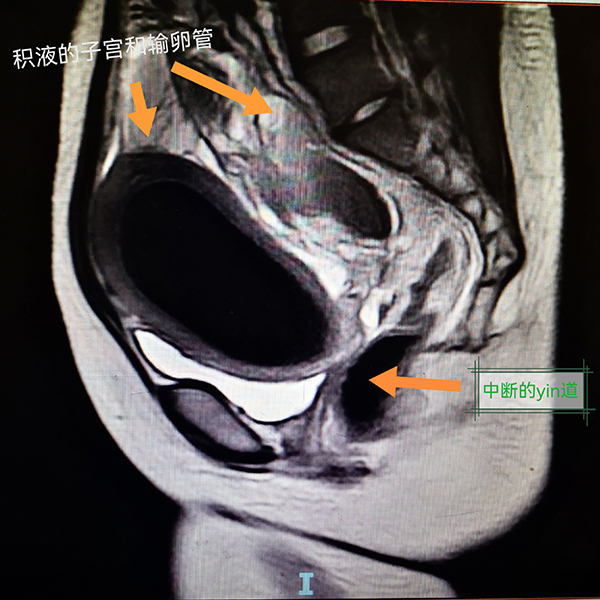

入院后,小杨进一步完善了腹部MRI等相关检查,结果显示她的病情比医生预知的情况更复杂。小杨的阴道只有约1cm长,宫颈阴道全程实性梗阻;盆腔增强磁共振考虑宫颈、阴道发育异常,宫颈闭锁可能,伴宫腔积液/积血;左下腹-盆腔内良性囊性肿块,考虑左侧附件来源病变,出血性囊肿可能;双侧输卵管扩张、积液/积血;考虑盆腔包裹性积液,伴盆腔腹膜渗出改变。经过多学科联合诊疗,医生决定为小杨实施经阴道阴道成型术+宫颈探查+成型术+腹腔镜探查+左侧卵巢囊肿剔除+双侧输卵管伞端造口+肠粘连松解术。

此次手术复杂且难度高,由在生殖道畸形手术方面具有丰富经验的杨岚副主任医师团队实施。术中,医生看到小杨盆腔内广泛粘连、多发包裹性积液(陈旧性血液),双侧卵巢见多个巧克力囊肿,双侧输卵管明显充血肿胀,子宫明显增大。阴道口探入最深1cm,之后阴道结构完全封闭消失形成盲端,未见宫颈结构。在腹腔镜的直视下,B超引导下探针进入宫腔,陈旧的巧克力样积血喷涌而出,残留4年的经血终于顺利流出。同时,腹腔镜下手术逐渐恢复小杨的正常解剖结构。反复下腹痛的“老问题”终于解决了,术后小杨说自己终于睡了个好觉,她母亲脸上也露出了久违的笑容。